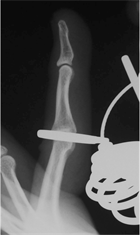

measurements. The minimum number of the ring gauge size that allowed the IP thumb joint and PIP finger joints, from the index finger to the little finger, to pass through was recorded. The positions that were actually measured by the ring gauges were the site at which weak resistance occurred (Figure 2(a)), the site at which maximum resistance occurred (Figure 2(b)) and the site at which resistance was attenuated (Figure 2(c)) when the finger was inserted into the ring. We measured the point at which there was maximum resistance, i.e. at Figure 2(b). RG was defined as the ring gauge number with the same diameter as the circumference of the IP thumb joint and PIP finger joints from the index finger to the little finger.

(a) (b) (c)

Figure 2. Measurement position for the ring gauge, (a) Distal end causing resistance; (b) Position at which maximum resistance occurs; (c) Position has passed the proximal part of the PIP.